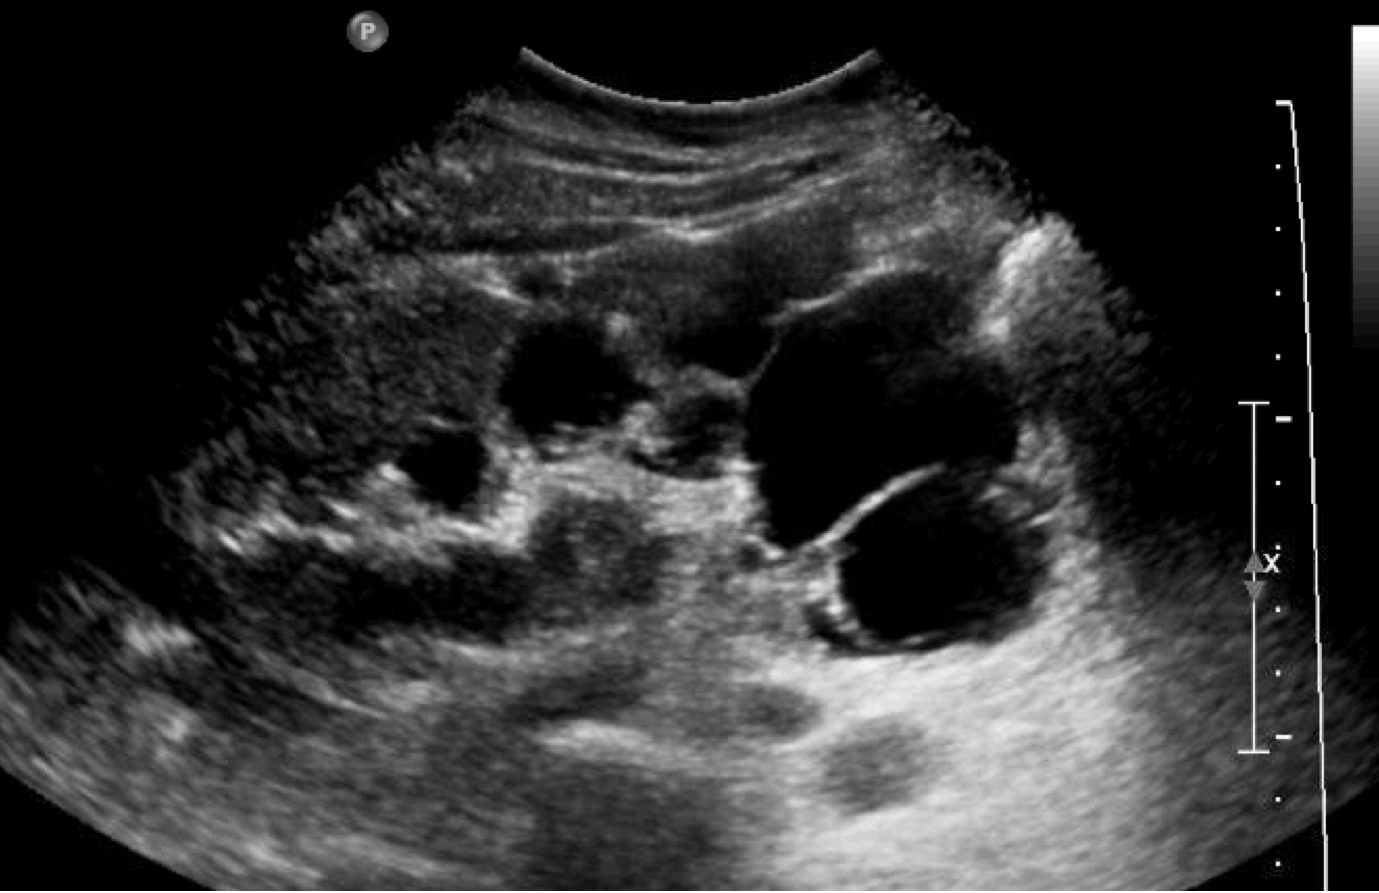

Diagnosis: Autosomal dominant polycystic kidney disease (ADPKD)

Case Summary: In this case, we have a patient with microscopic hematuria, complaints of thirst and polyuria, a biological parent with a history of end stage kidney disease, and fullness of the flanks on physical exam. The kidney ultrasound confirms a classic presentation of ADPKD. Other diagnoses high on the differential would include thin basement membrane disease, Alport’s syndrome (though no history of hearing loss here), and IgA nephropathy – though these would not produce flank fullness.

Our patient had numerous cysts in both kidneys. Other features of ADPKD include proteinuria (due to impaired low-molecular weight protein tubular endocytosis and reabsorption), hematuria, nephrolithiasis (stones), and thirst/polyuria/nocturia (present in our patient) due to a urine concentration defect. These patients may also develop cyst hemorrhage or infections, renal carcincoma, or abdominal pain from large kidney size. Cysts that form in the liver can also cause abdominal pain. Take a look at an ultrasound and CT image from two patients with ADPKD below: